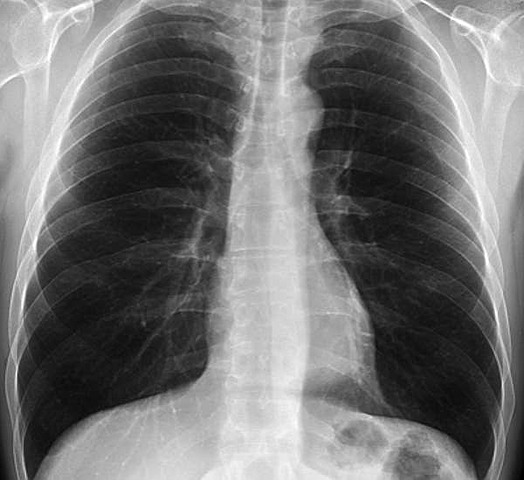

• Avances en la Radiología Pulmonar

Avances en la Radiología Pulmonar

El radiólogo estadounidense Henry K. Pancoast realizó avances innovadores en este campo. De hecho, fue el primer profesor de radiología en los Estados Unidos, nombrado en 1912 en la Universidad de Pensilvania. Ese mismo año, fue elegido presidente de la Sociedad Americana de Rayos Roentgen.

A lo largo de las décadas de los veinte y los treinta, hubo una mejora constante en la pantalla de intensificación y las placas radiográficas que contribuyó a mejorar las imágenes del tórax.